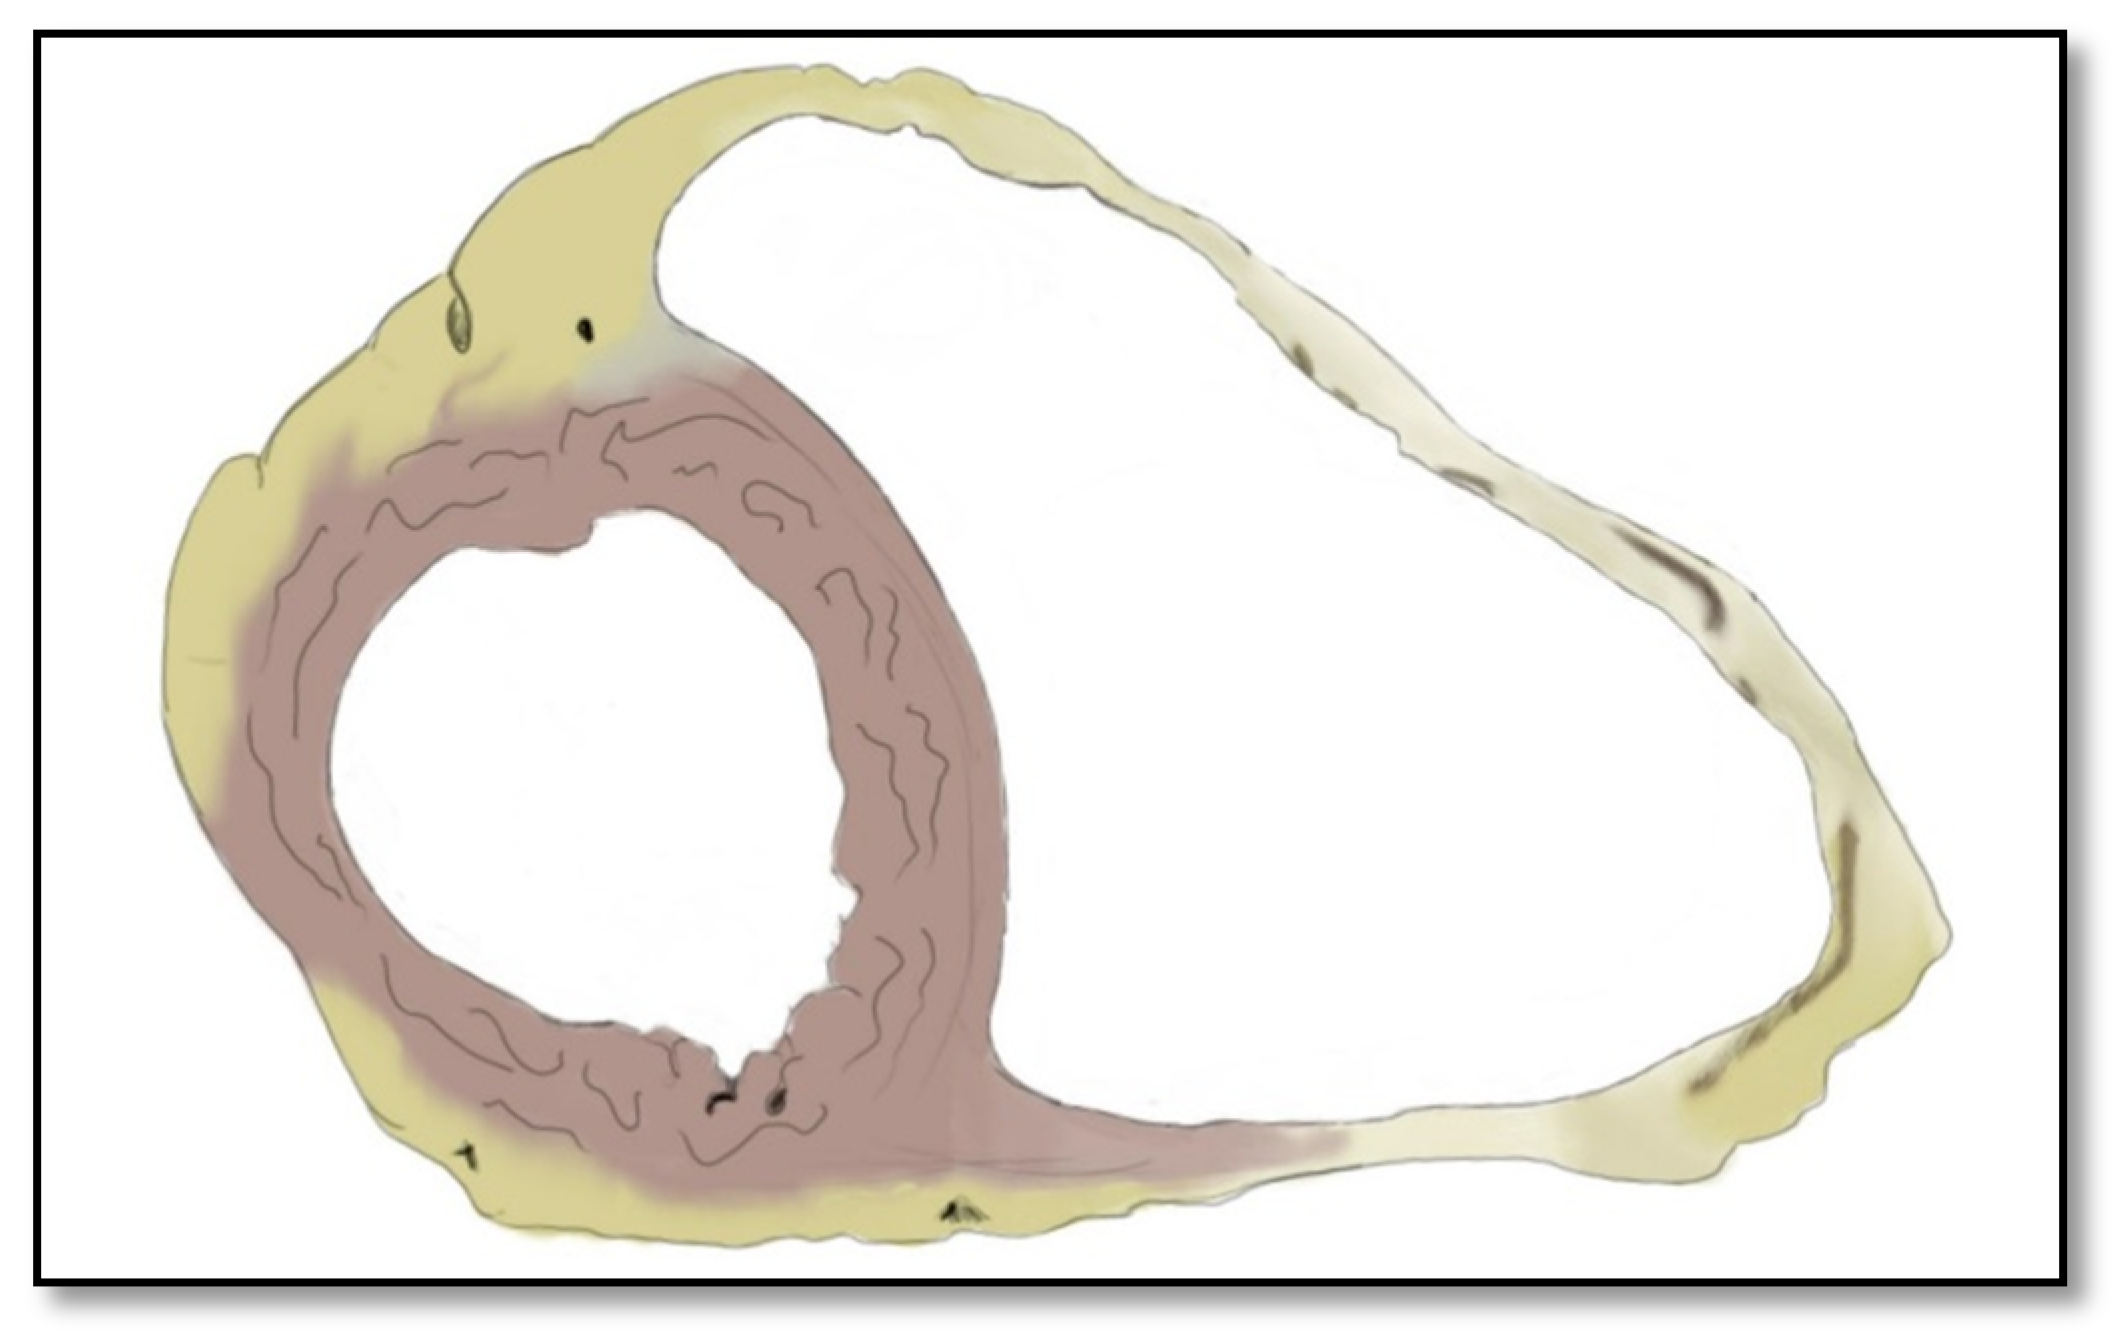

2.1. Right Ventricle Pathological Features in ARVC

- Intramyocardial adipose tissue disposition—”obsolete”Although intramyocardial fat has long been a diagnostic criterion for ARVC, it is no longer used because other pathological or physiological conditions can lead to this appearance in cardiac MRI. In normal people, epicardial fat can penetrate to the myocardium and endocardium, with no clear demarcation between the epicardium and the myocardium, leading to misinterpreted images as ARVC. When intramyocardial fat is detected, it will be considered pathological only if it is associated with contraction abnormalities of the corresponding wall [12,45].Fat in ARVC appears as hyperintense intramyocardial signal at T1 spin-echo. Adipose tissue infiltrates mainly the RVOT, the free wall of the right ventricle, the intracavitary trabeculae, the moderating band, and the right side of the interventricular septum (Figure 4).Tansey et al. showed on autopsies of individuals without known heart disease that 85% of them had myocardial infiltrates with adipose tissue [46]. Mainly, the RVOT, free wall of RV wall, apex, and RV antero-lateral wall are affected, but these intramyocardial deposits do not change the thickness of the ventricular wall or the regional contraction. If the deposits extend from the epicardium to the endocardium, crossing the myocardium, then the ventricular wall may increase in size as a normal feature of the adipose distribution. It seems that these fat deposits in healthy people increase with age and are more common in obese people without being pathological [47].